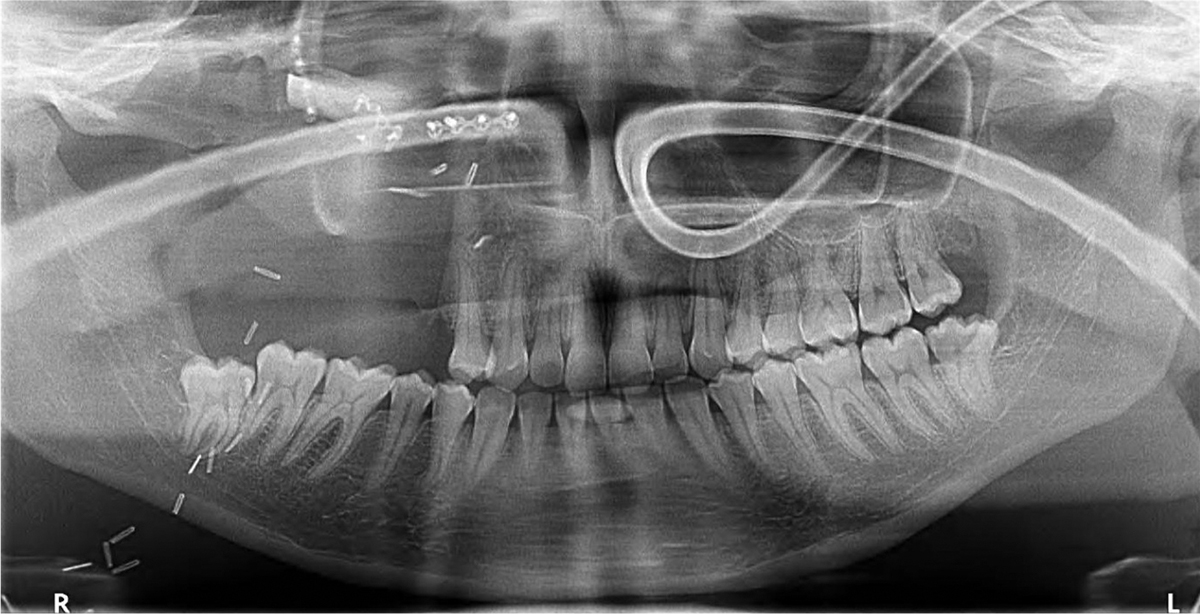

Postoperative panoramic radiograph showing the post-surgical defect classified as a Brown III-b class.